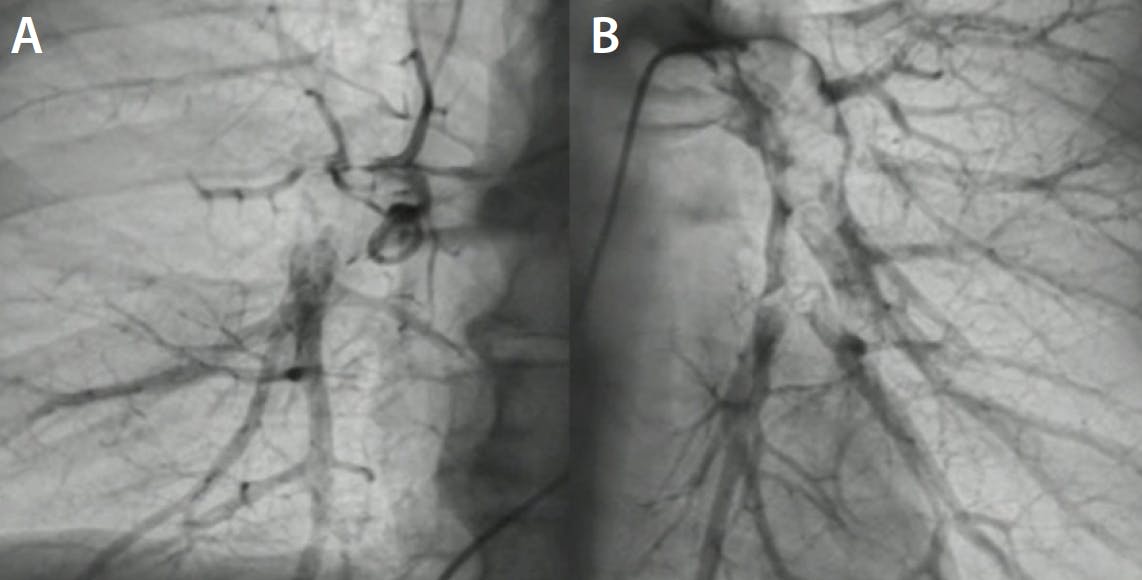

Figure 2. Pretreatment pulmonary angiography of the right (A) and left (B) PA.

Figure 3. Navigation in the right PA (A) and Flash catheter in the left PA (B).